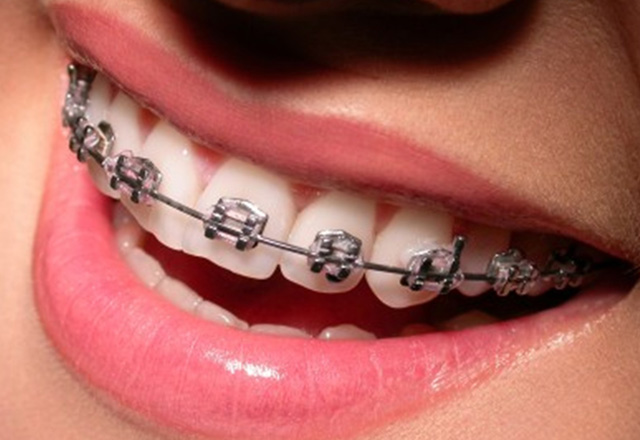

Orthodontics and dentofacial orthopaedic treatment deals with the correction of irregular and malplaced teeth and also corrects the facial deformities ...